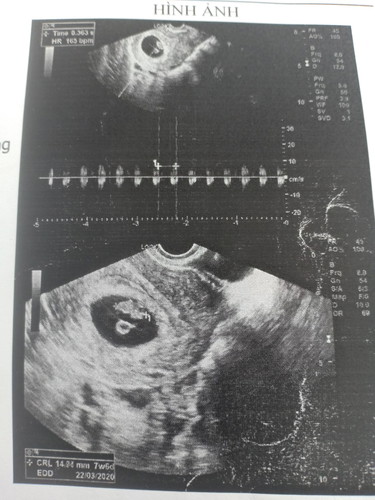

Em bầu được 8 tuần siêu âm ra hình thấy phôi thai lệch sang bên trái vậy là thai nằm ở bên bụng trái phải ko ạ? E ko biết hình siêu âm với thực tế có ngược chiêù nhau ko mà quên hỏi bsi. E muốn biết để tránh nằm nghiêng sang phía của em bé. Các mẹ giải đáp giúp e với, thanks.

Em nghĩ là thai nằm bên phải á. Vì lúc bs siêu âm sẽ tương ứng với vị trí bụng của mình mà